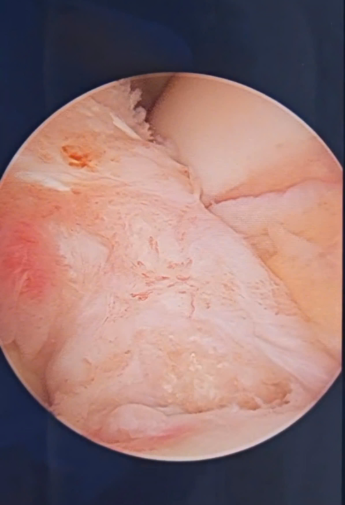

Hình 3. (Hình ảnh trong mổ) Dây chằng chéo trước mới được tái tạo bằng phương pháp bảo tồn di tích dây chằng cũ.